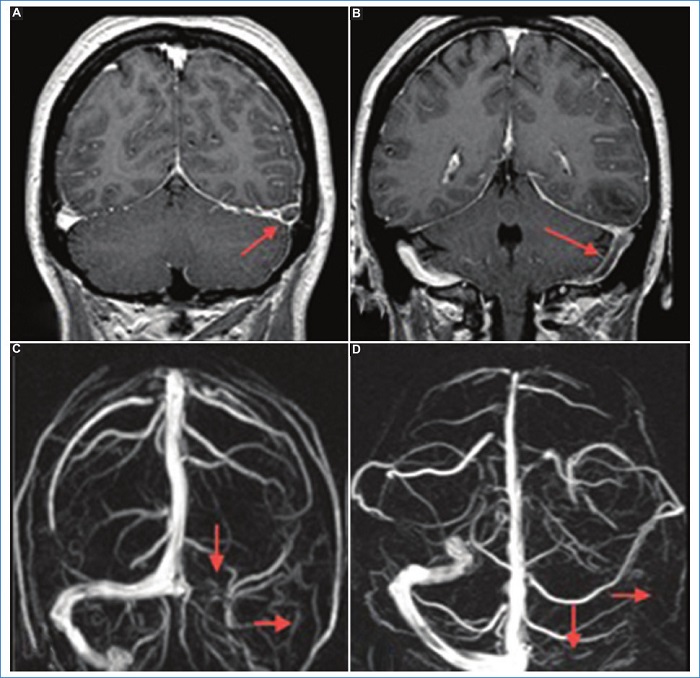

RM: es el método de elección. Se observan engrosamiento y realce difuso dural en el 85% de los casos (Fig. 6), que puede asociarse a colección subdural, descenso de las amígdalas cerebelosas y con menor frecuencia a signos de ingurgitación venosa4,11.